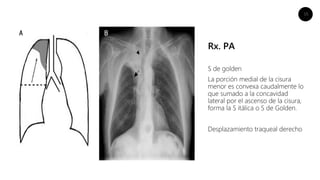

Rx. PA

S de golden

La porción medial de la cisura

menor es convexa caudalmente lo

que sumado a la concavidad

lateral por el ascenso de la cisura,

forma la S itálica o S de Golden.

Desplazamiento traqueal derecho